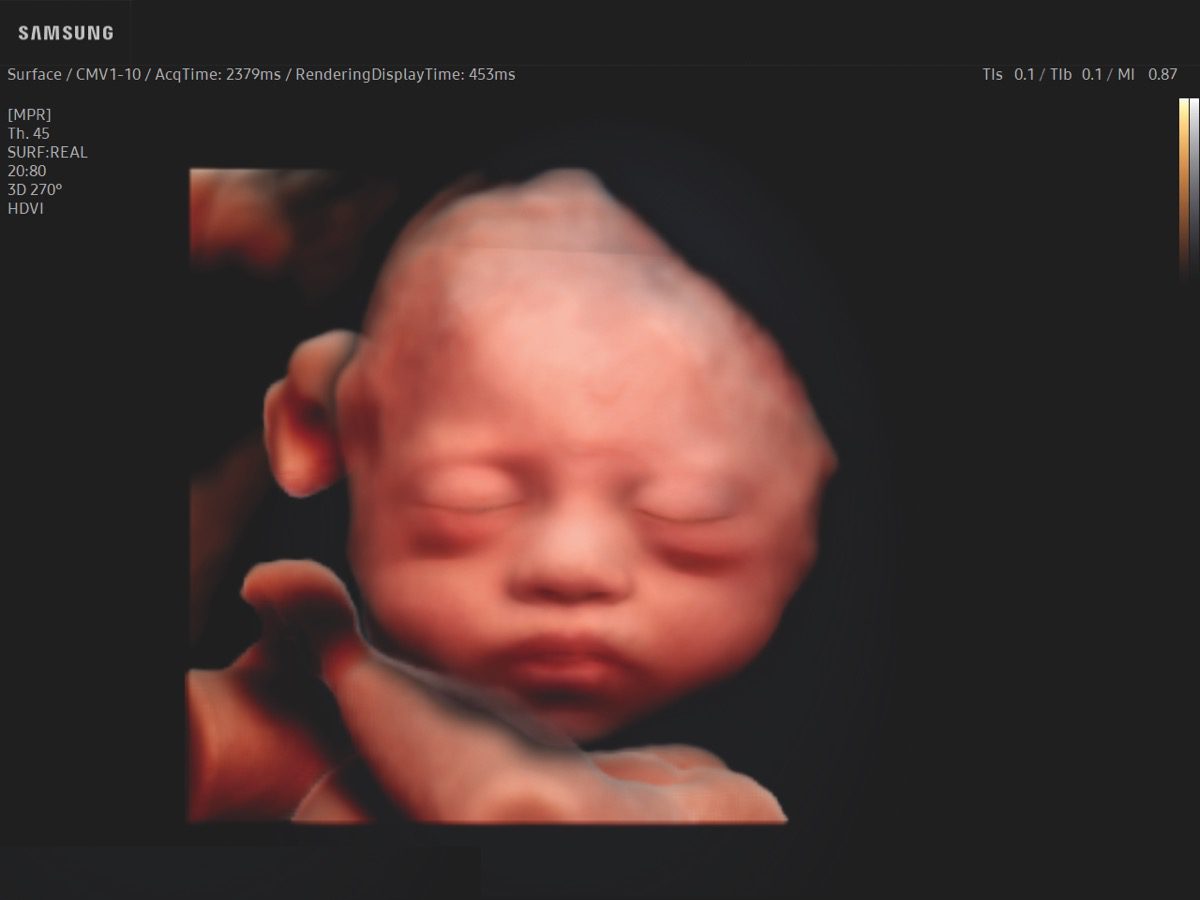

Comprehensive, advanced and expert MFM care for high-risk pregnancies

- Fetal anomalies